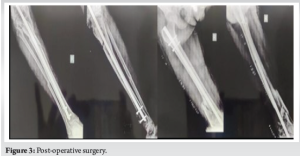

The patient was followed up for at least 4 months postoperatively (Fig 3 and 4). Serial radiographs showed callus formation at the distal femur, but incomplete consolidation at the docking site. There was partial resolution of infection and improvement in soft-tissue status.